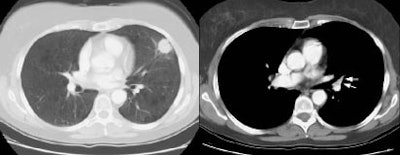

Example of the normal hilar interstitium: The images below are from a patient without bronchogenic carcinoma. The images demonstrate normal hilar lymphatic tissue (yellow arrow right image) which appears as a low density region between the bronchus and pulmonary vessel. A small calcified node is seen on the right (red arrow) in this patient with prior granulomatous disease.   NOTE:  Click image to enlarge.

Recently it has been proposed that with the use of helical CT the standard criteria for abnormal nodes (i.e., size greater than 1 cm) lacks sensitivity for the presence of hilar adenopathy [36]. The normal peribronchovascular interstitium adjacent to the hila contains lymph nodes and normally has a concave or straight margin with the adjacent lung parenchyma [38] and this finding is not affected by the level of pulmonary distention. By using the presence of a convex margin of the interstitium with the adjacent lung parenchyma to indicate the presence of hilar metastases, a sensitivity of 87% can be achieved (specificity 88%, and accuracy 88%) [36]. This criterion has also been shown to have good interobserver agreement. In another study of the peribronchovascular interstitium and hilar lymph nodes by spiral CT, it has also been suggested that a short axis diameter of greater than 3 mm be considered abnormal, but further studies have yet to confirm this criterion [39]. A limitation of either of these criteria is that other conditions can also produce the presence of adenopathy with convex bronchovascular margins or increased transverse diameter including sarcoidosis, bronchiectasis, chronic bronchitis, and interstitial fibrosis [36].